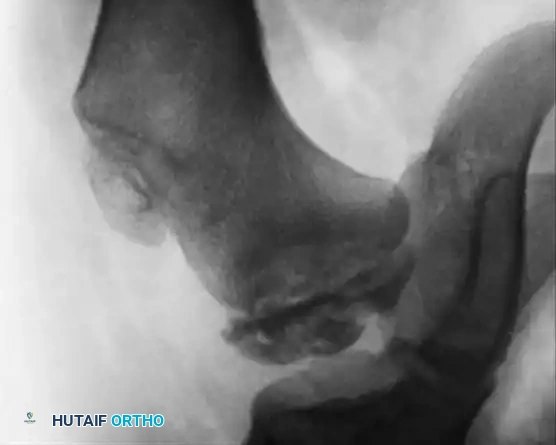

Hemophilic pseudotumors are rare but limb-threatening complications caused by recurrent bleeding into muscles or subperiosteal spaces, leading to pressure necrosis of adjacent bone. In the pediatric hip, recurrent bleeding can compromise the vascular supply to the femoral head, leading to changes indistinguishable from Legg-Calvé-Perthes disease or severe osteochondritis dissecans.

Fig. 29-34: Progression of osteochondritis dissecans of the hip in a hemophilic patient. Note the onset of Perthes-like disease, fragmentation, reossification, and eventual healing over an 8-year period, demonstrating the profound impact of intra-articular pressure and vascular compromise on the developing femoral head.